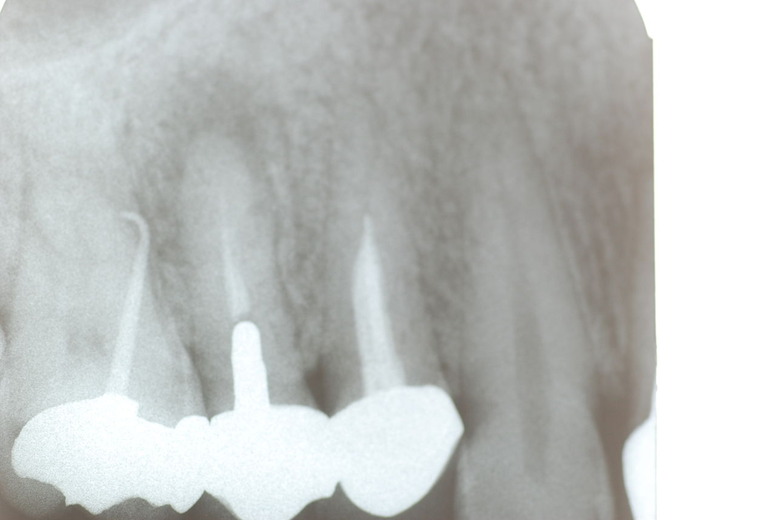

写真左下の親知らずが痛くなり抜歯しました。その後歯茎を除去して虫歯を露出させる処置を二回ほどしています。

レントゲンでは小さいですが、こう言う虫歯が一番怖いのです。

隣の14歳大臼歯がひどい虫歯になり治療不可能になりつつある状態のレントゲン